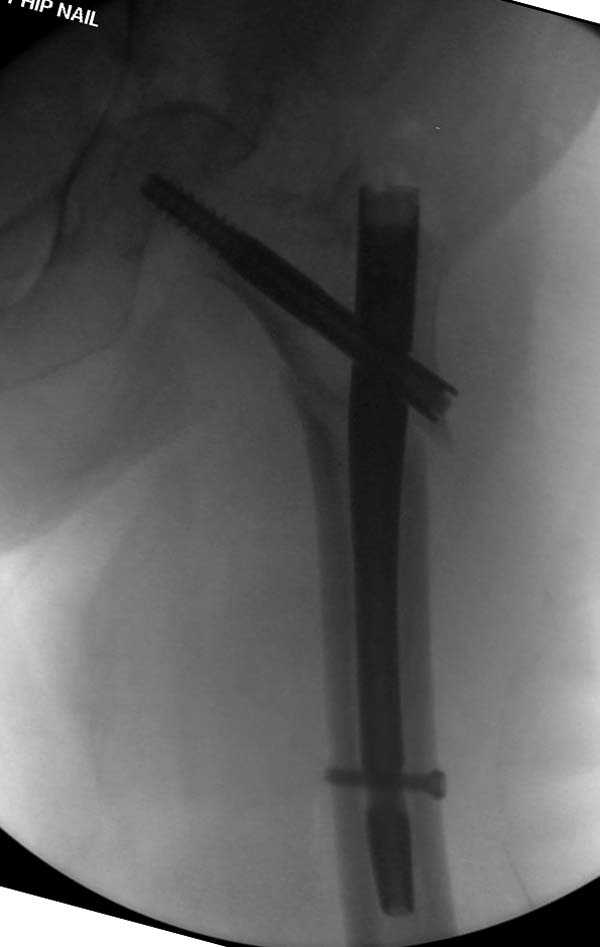

Здесь представлен случай, где в послеоперационном периоде обнаружена техническая ошибка, Gamma 3 установлен с нарушением методики. Больная в 91 лет, прооперирована через день после поступления и выписана через 48 часов.<br>

При первом послеоперационном поликлиническом осмотре больная предъявила жалобы на боли в бедре. В серийных снимках обнаружен продольный перелом верхнего отдела бедра.<br>

Считаем, что техническая ошибка произошла во время установки гвоздя, когда рассверливанию канала не уделили должного внимания. Канал остался узковат, и гвоздь был забит с силой.

Полная нагрузка конечности приостановлена на две недели, и боли в конечности изчезли. Больная начала нагрузку и перелом срастается.

Имя     : Gamma 3. 6.jpg